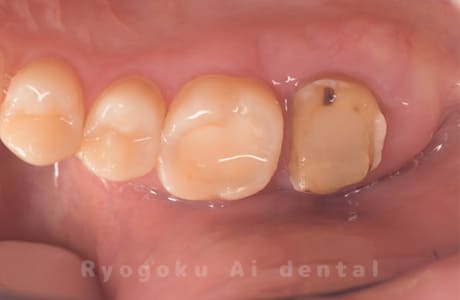

Case08

-

- 原因

- 歯根嚢胞、重度カリエス

- 治療内容

- 再植手術、クラウンレングスニング

- 治療費用

- ¥99,000

他院で根管治療を行ったが、なかなか治らず、抜歯を宣告されたとのことでご来院された患者様です。歯がかなり削られており、また、歯根の根尖部の病変が大きく、嚢胞化しているため、クラウンレングスニングと再植歯根端手術を同時に行いました。違和感もなくなり、大変満足されています。

<リスク・副作用>

外科手術のため、術後に出血、痛みや腫れ、違和感を伴います。口腔内の状態によっては適応できないことがあります。歯根端切除で治らなければ抜歯を検討しなくていけない場合もあります。